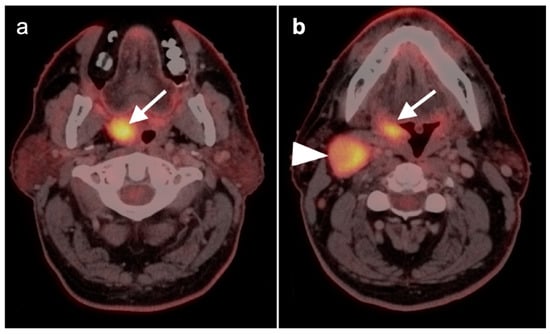

2.2. Squamous Cell Carcinoma of the Head and Neck (SCCHN)